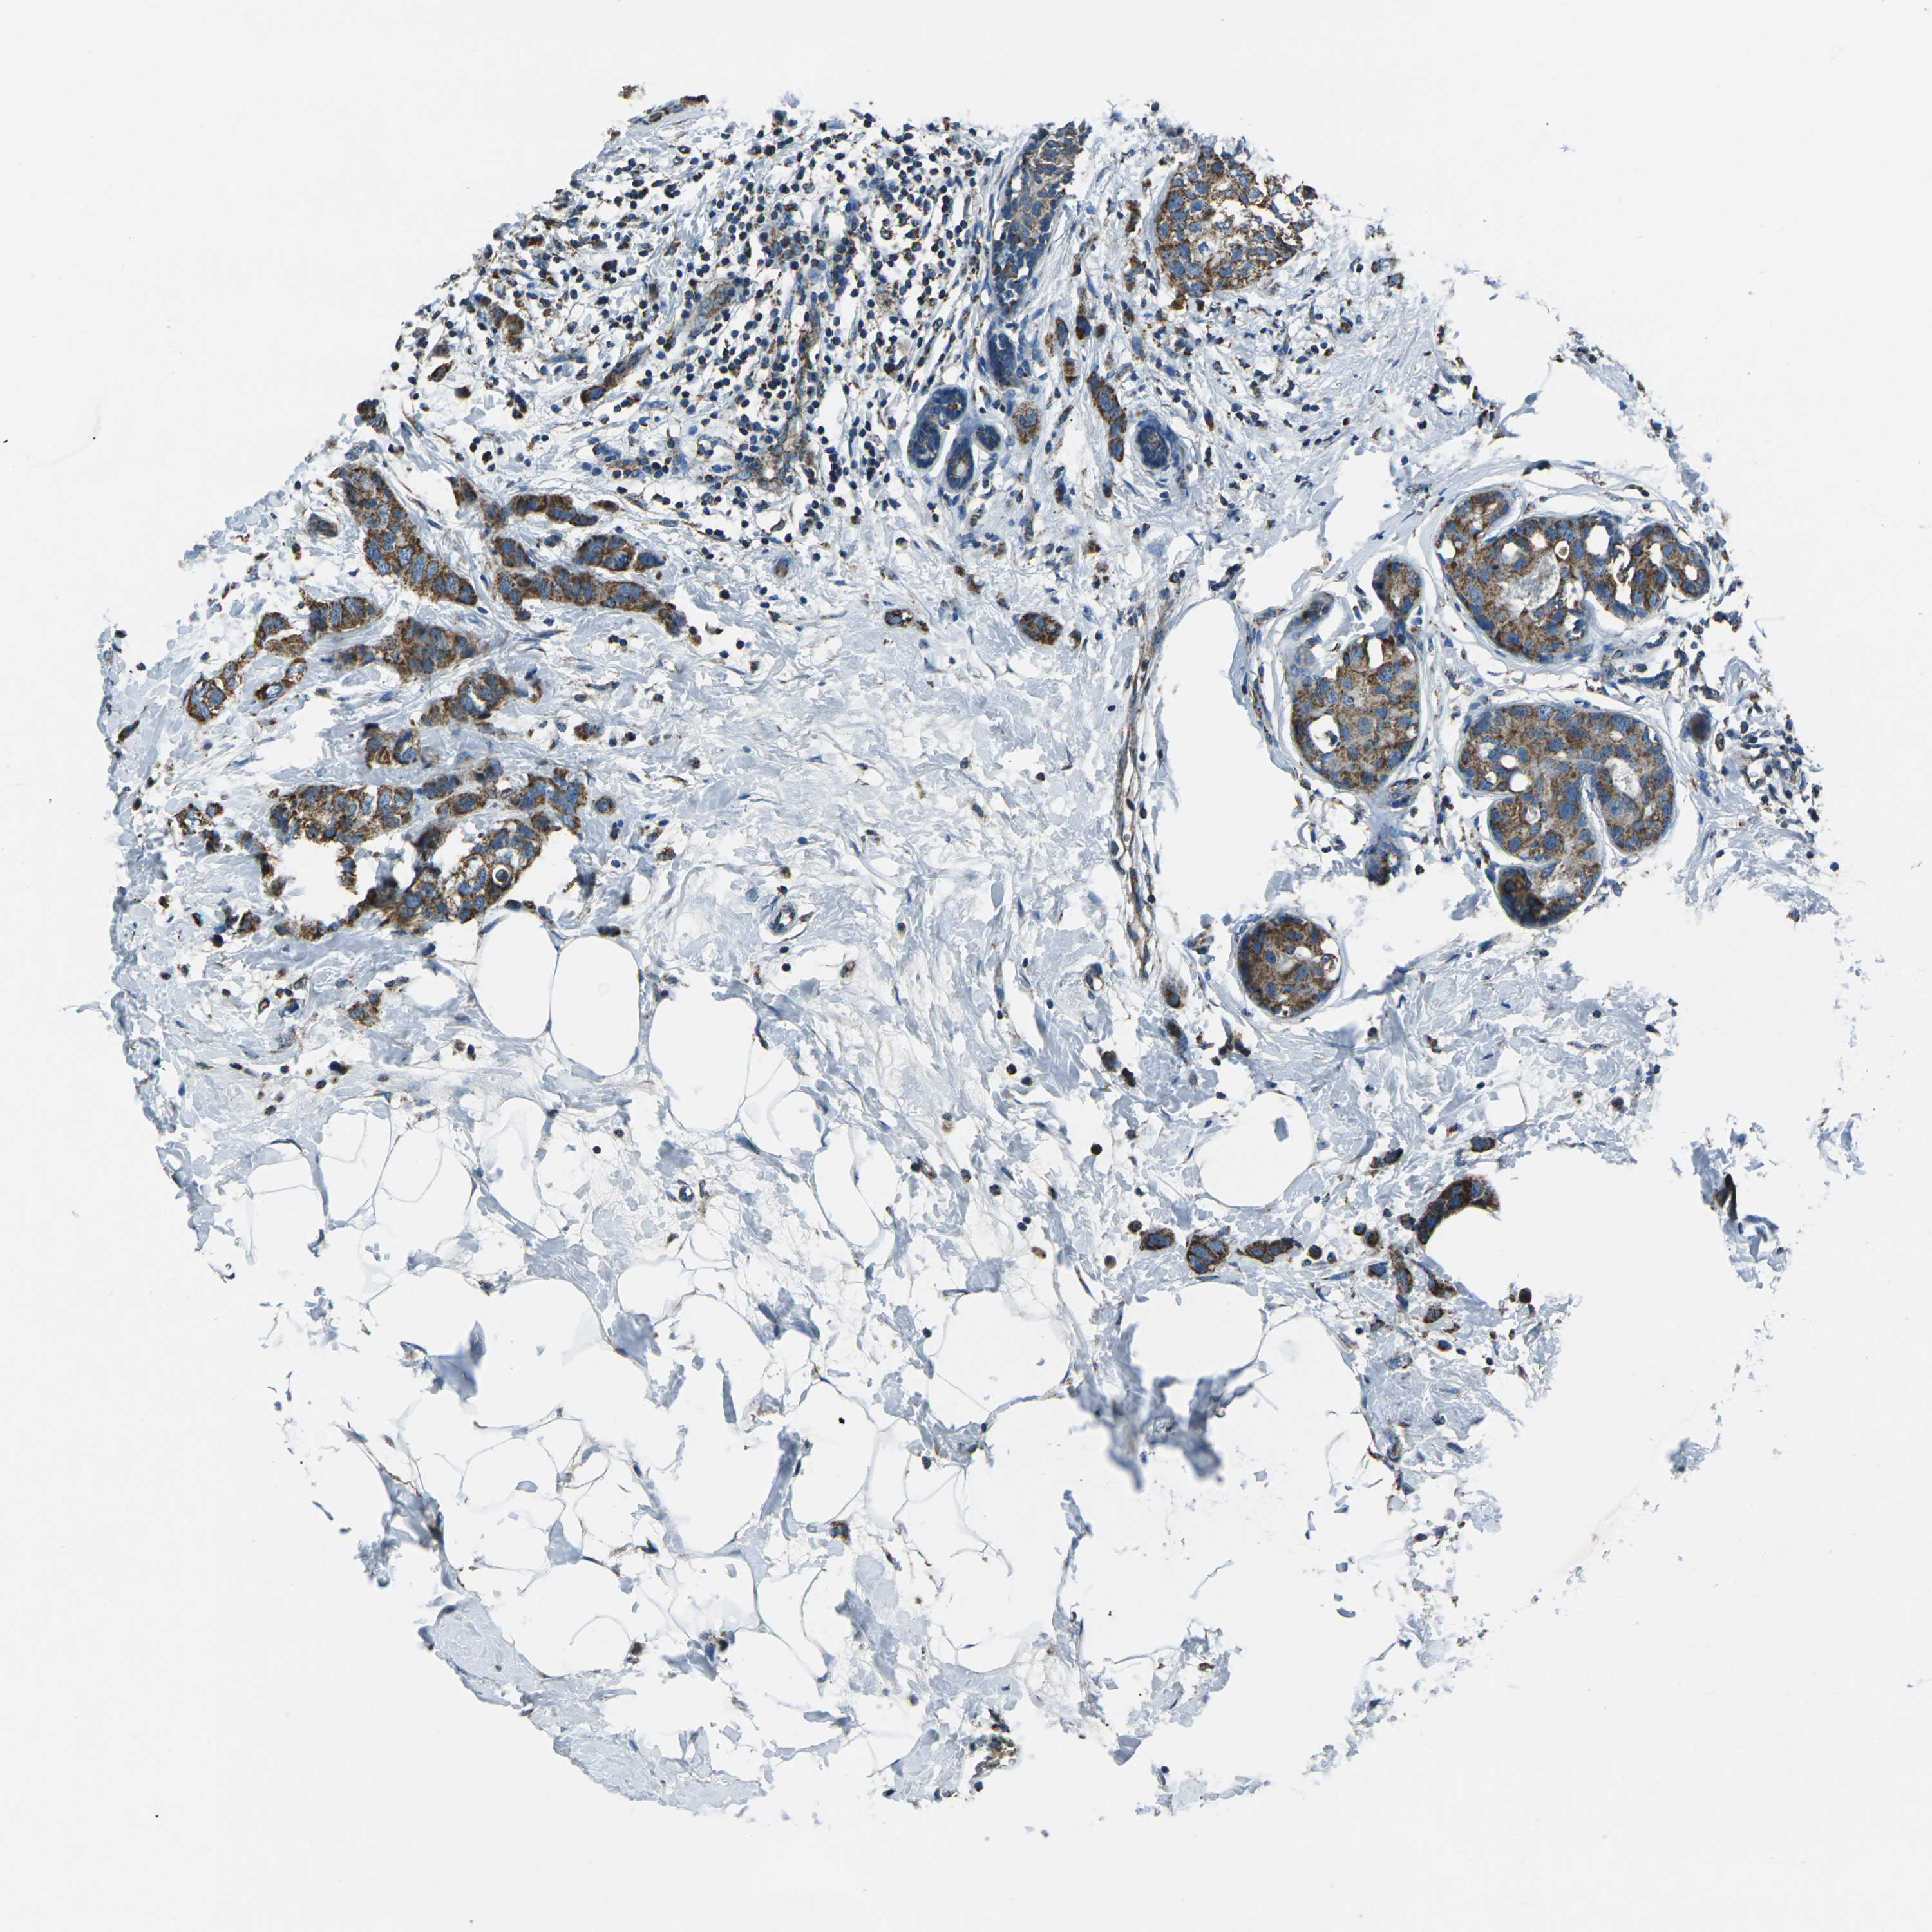

CANCER BREAST CANCER Show tissue menu

BRCA TCGA BRCA VALIDATION PROTEIN EXPRESSION

ANTIBODIES

AND

VALIDATION